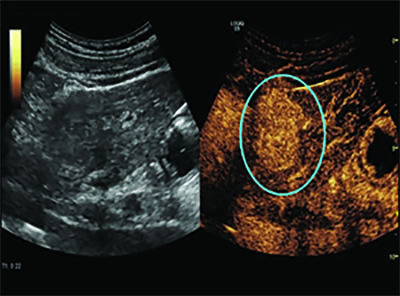

The use of oscillating microbubbles as pressure sensors could also provide early indications of the effectiveness of chemotherapy in treating breast cancer. The approach takes advantage of the fact that interstitial fluid pressure is significantly higher in a tumor than in normal tissue.

A 2017 study in Radiology found that SHAPE was able to predict treatment response in breast cancer patients with 100 percent accuracy after just one round of chemotherapy. (See Web Extras.)

“We see this as an indication that the pressures inside the tumor have dropped, these vessels have opened up and you’re getting more signal in there,” Dr. Forsberg said. “This is an indication that chemotherapy is working.”